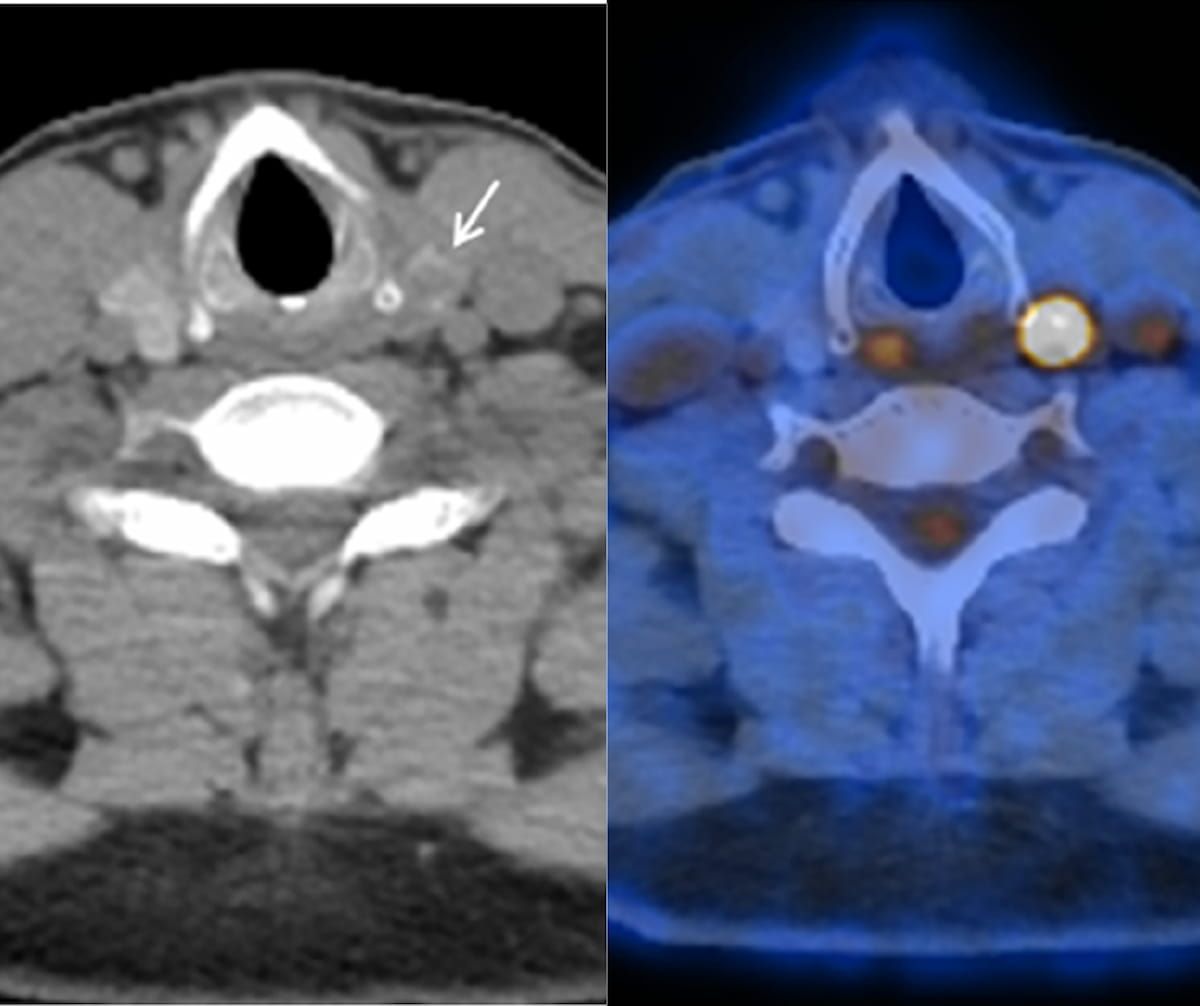

Utilizing the AI-enabled TrackPSMA to monitor the effectiveness of radioligand therapy for prostate cancer may allow more timely decisions to adjust treatment dosage or switch to a more effective modality.

In a prospective study comparing PSMA PET/CT and mpMRI for biopsy- and imaging-naïve men with suspected prostate cancer (PCa), PSMA PET/CT led to altered management in 34 percent of confirmed cases of PCa.

In the 160-patient study comparing 18F-PSMA 1007 PET/CT and 18F-NaF PET/CT, the use of 18F-PSMA PET/CT led to 38 patients being restaged as having more advanced prostate cancer.

PSMA PET offered 18 percent higher accuracy for detecting biochemical recurrence of PCa in contrast to mpMRI, according to findings from a 67-study meta-analysis.